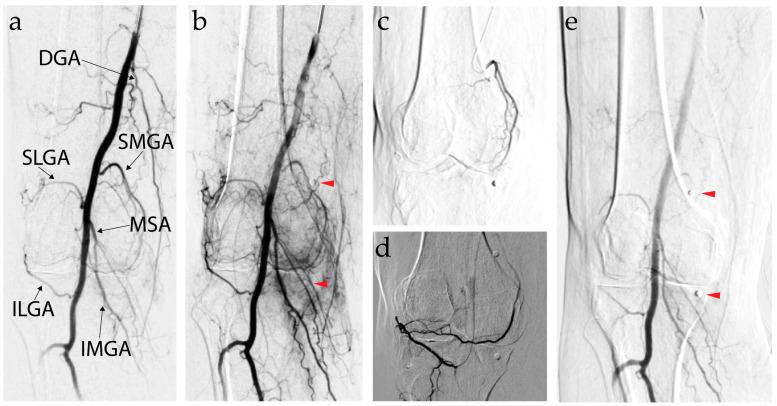

Genicular Artery Embolization: A Review of Essential Anatomic Considerations.关节动脉栓塞术:重要解剖学考虑因素的综述。

J Vasc Interv Radiol. 2024 Apr;35(4):487-496.e6. doi: 10.1016/j.jvir.2023.12.010. Epub 2023 Dec 19.